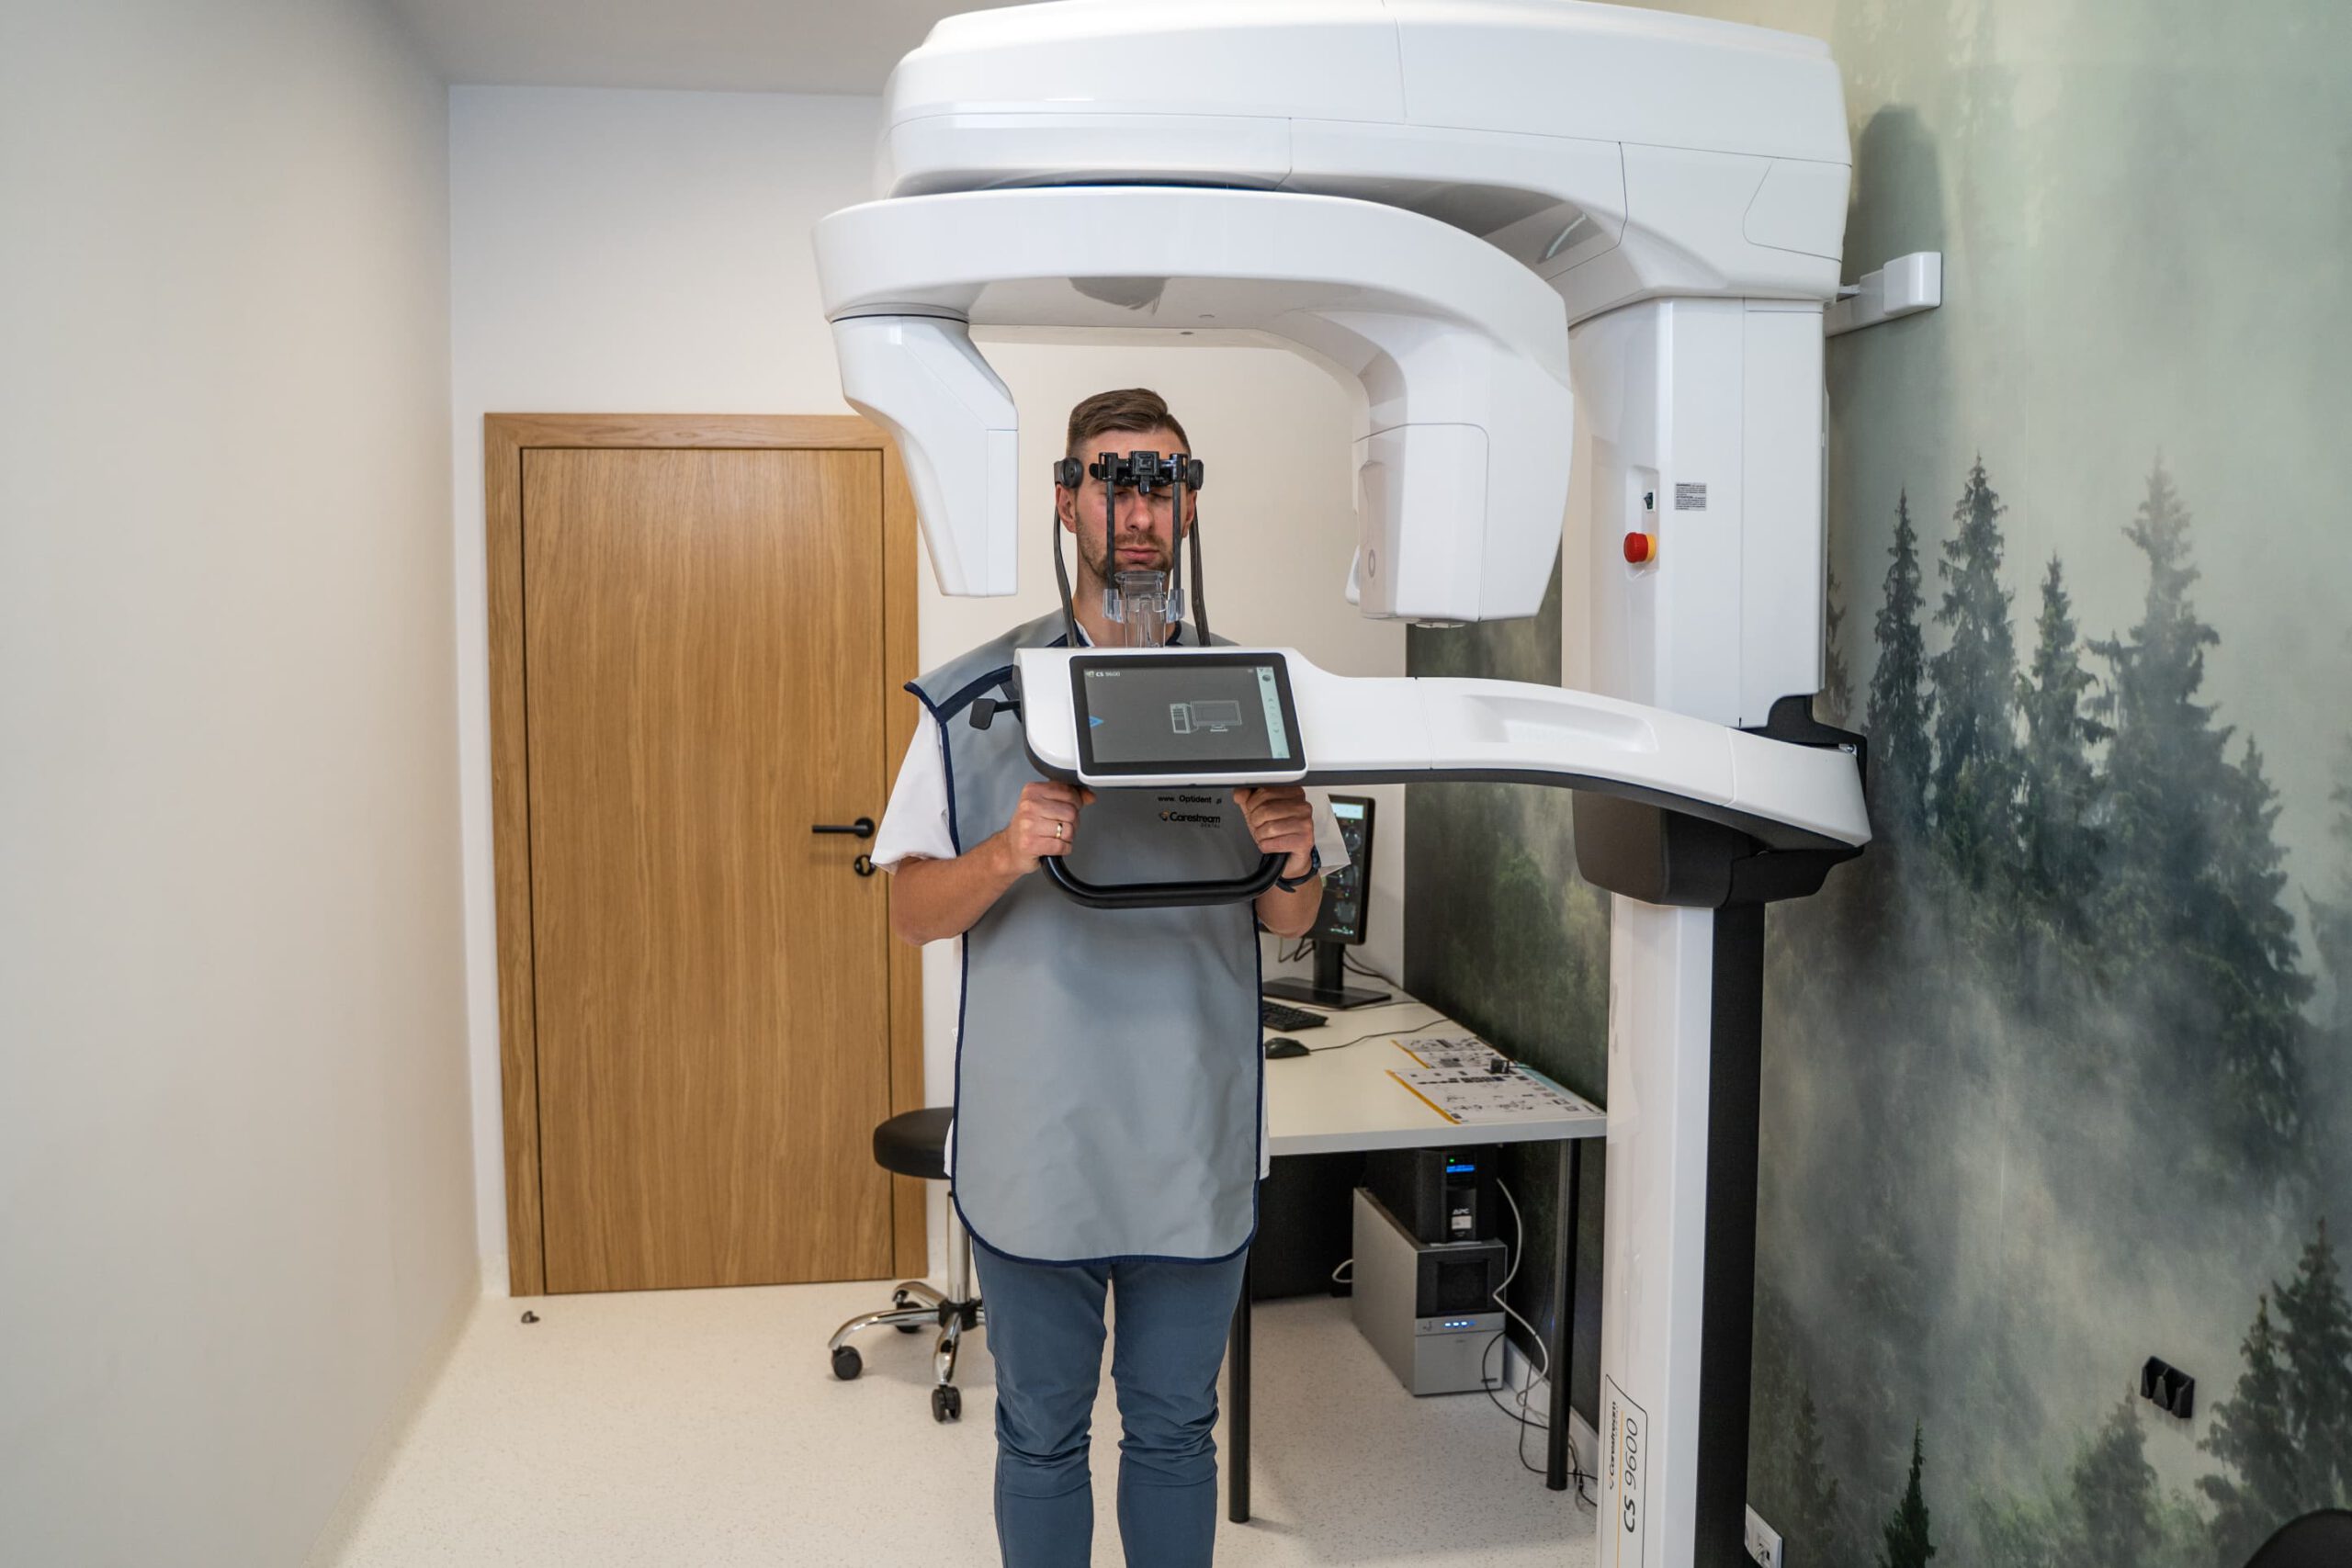

Tomograf Kodak Carestream CS 9600 jest to system, który zapewnia najwyższą dostępną jakość uzyskiwanych obrazów oraz aż czternaście różnych pól obrazowania. Zastosowane w nim innowacyjne rozwiązania pozwoliły na osiągnięcie doskonałych efektów, przy jednoczesny zwiększeniu bezpieczeństwa użytkowania. Dzięki licznym funkcjom sprawdza się jako urządzenie diagnostyczne w wielu dziedzinach stomatologii. Tomografia wykonana przy jego użyciu jest przy tym wyjątkowo dokładna. Oznacza to, że podczas badania można bardzo precyzyjnie zobrazować wszystkie tkanki organizmu – to pozwala na szybkie postawienie jednoznacznej diagnozy oraz natychmiastowe wdrożenie odpowiednich metod leczenia.

Tomograf Kodak Carestream CS 9600 jest to system, który zapewnia najwyższą dostępną jakość uzyskiwanych obrazów oraz aż czternaście różnych pól obrazowania. Zastosowane w nim innowacyjne rozwiązania pozwoliły na osiągnięcie doskonałych efektów, przy jednoczesny zwiększeniu bezpieczeństwa użytkowania. Dzięki licznym funkcjom sprawdza się jako urządzenie diagnostyczne w wielu dziedzinach stomatologii. Tomografia wykonana przy jego użyciu jest przy tym wyjątkowo dokładna. Oznacza to, że podczas badania można bardzo precyzyjnie zobrazować wszystkie tkanki organizmu – to pozwala na szybkie postawienie jednoznacznej diagnozy oraz natychmiastowe wdrożenie odpowiednich metod leczenia.

W zależności od rozmiaru zdjęcia, tomograf Kodak Carestream CS 9600 emituje od 5 do 14-19 μSv promieniowania rentgenowskiego, co jest dawką nawet o 85% niższą niż w przypadku innych sprzętów. Co istotne, tomograf Kodak Carestream CS 9600 jest idealny do badań typowych dla każdej specjalizacji stomatologicznej oraz laryngologicznej (badanie zatok przynosowych lub skalistości kości skroniowych). Sprawdzi się w przypadku pacjentów implantologicznych, ortodontycznych, periodontologicznych, endodontycznych czy chirurgicznych.